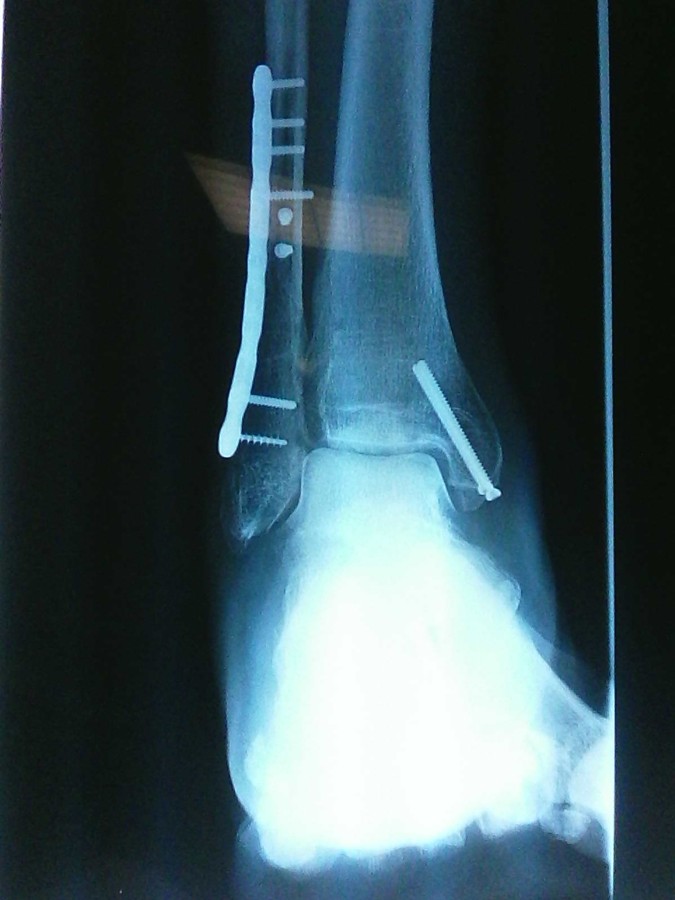

A la demande de Lucien 79, la samba des osselets !!!

Bien ferraillé le Lulu !!!

Bon courage pour la rééducation

moonarise a écrit :Justement, Jean-François...J'ai regardé!...Manquerait pas une petite vis tête fraisée entre la malléole interne et l'astragale?